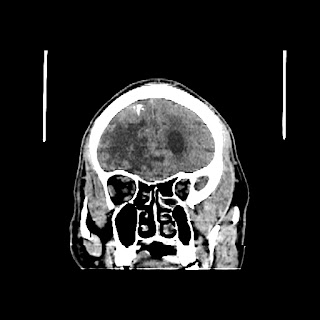

A 60 years old man with seizure since 12 years

Plan CT scan was done on 22 march 2016